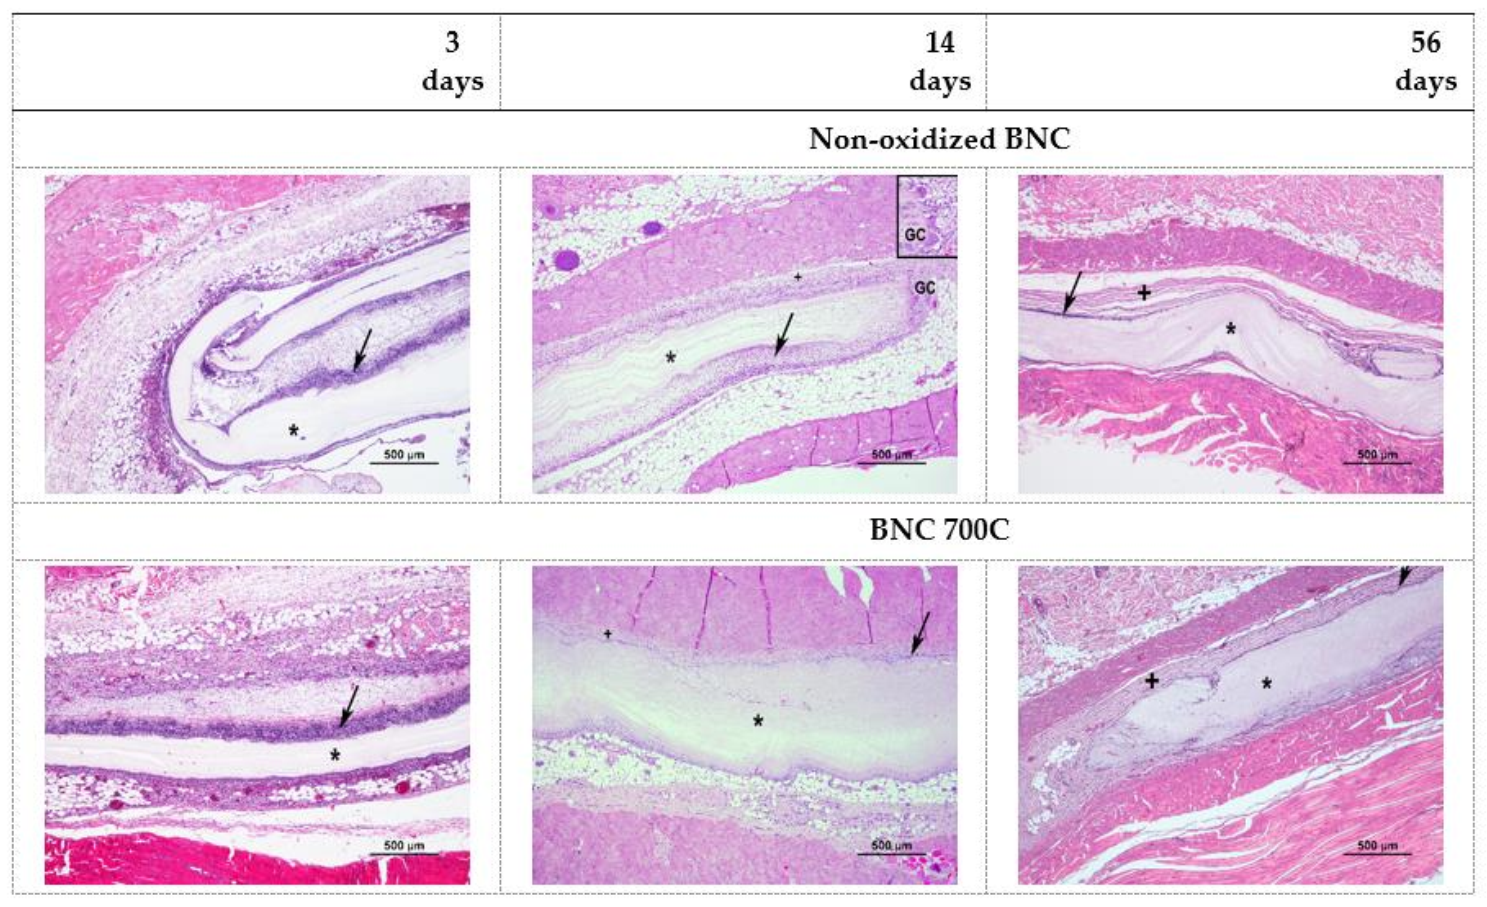

3.10. In Vivo Biocompatibility of BNC Membranes

| 3 days | 14 days | 56 days | ||||

|---|---|---|---|---|---|---|

| NO BNC | BNC 700C | NO BNC | BNC 700C | NO BNC | BNC 700C | |

| Polymorphonuclear cells | 4 | 2 | 3 | 2 | 1 | 1 |

| Lymphocytes | 2 | 2 | 2 | 2 | 2 | 2 |

| Plasma cells | 1 | 0 | 1 | 0 | 0 | 0 |

| Macrophages | 2 | 1 | 2 | 2 | 2 | 2 |

| Giant cells | 0 | 0 | 1 | 1 | 1 | 0 |

| Necrosis | 2 | 0 | 0 | 0 | 0 | 0 |

| Neo vascularization | 2 | 0 | 1 | 0 | 0 | 0 |

| Fibrosis | 0 | 0 | 1 | 3 | 3 | 4 |

| Fatty infiltration | 0 | 0 | 0 | 0 | 0 | 0 |